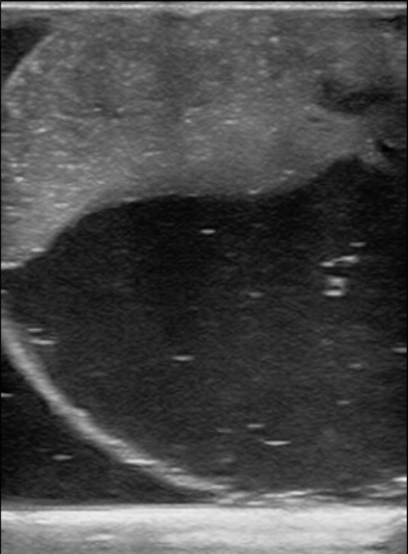

Figure 14. A model created with half the recommended gelatin concentration used as an example of testicular Infarction with hydrocele. The model was allowed to settle in place in the refrigerator and the psyllium collected to one side.